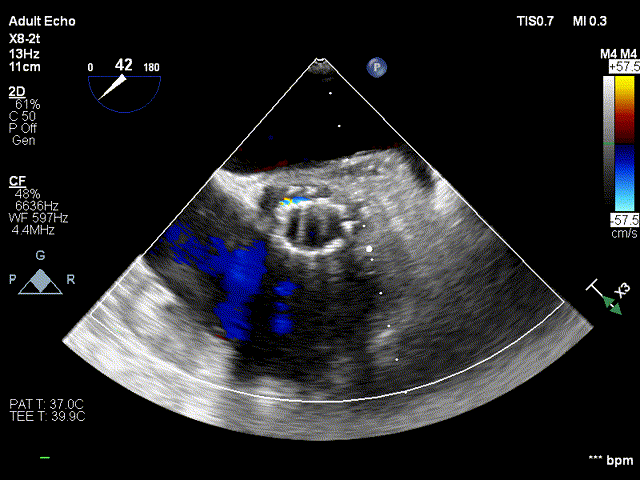

术前超声

术前超声-短轴切面

术前超声-长轴切面

术后超声:

术后超声-短轴切面

术后超声-长轴切面

术前跨瓣压差

术后跨瓣压差

随着TAVR技术在国内的普及,主动脉瓣狭窄患者有了更多的治疗选择。本例病人为主动脉瓣重度狭窄伴轻度反流,手术指征明确,患者明确拒绝外科手术,术前解剖形态评估适宜行TAVR手术,有TAVR手术指征。经罗骏、崔凯教授团队的综合评估,结合心内科、心外科、超声等多学科团队的讨论意见,最终决定为患者施行TAVR手术治疗。手术过程中,TaurusElite经导管主动脉瓣输送系统在保持回收性能稳定的同时兼具优异的柔顺性,顺利完成过弓、跨瓣操作。其次,针对本例患者钙化较重、瓣叶局部粘连的特点,TaurusElite瓣膜高密度流入端设计提供了足够的径向支撑力,保证了瓣膜的锚定力;低密度流出端的设计也兼具柔顺性,能帮助术者更好的完成过弓与跨瓣操作。此外,TaurusElite瓣膜内外双裙边设计能有效减少瓣周漏,适度的收腰既能保证足够的有效瓣口面积,又降低了冠脉阻挡风险。最后,面对临床复杂的解剖结构特点,瓣膜释放过程中可能出现瓣膜下滑或上跳的风险,增加了术中释放瓣膜的难度;而TaurusElite瓣膜系统具有多次原位回收、回收后可重新跨瓣等设计特点,让术者释放过程中更有信心,能降低手术风险,减少并发症的产生,从而让患者得到更好的预后。本例患者术中的情况验证了术前CT分析的准确性,最终瓣膜释放位置良好,冠脉血流灌注正常,术后压差明显降低,术后跨瓣压差从101mmHg降至2mmHg,仅有微少量瓣周漏。术后病人恢复良好,各项生命体征平稳,手术效果十分优异。